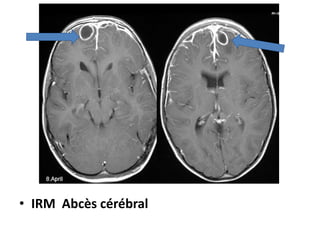

» IRM++++Examen de référence

• IRM: lésion en hyposignal T1, hypersignalT2

• Diffusion : hyper signal diffusion central ADC bas, lié au

contenu purulent(viscosité et hyper cellularité)

• Spectroscopie : étude des métabolites de l’abcés :Pic

d’acides aminés(Leucine, isoleucine,valine

• Effet de masse sur le système ventriculaire homolatéral

et les structures médianes

• IRM Abcès cérébral

TDM Abcès multiples